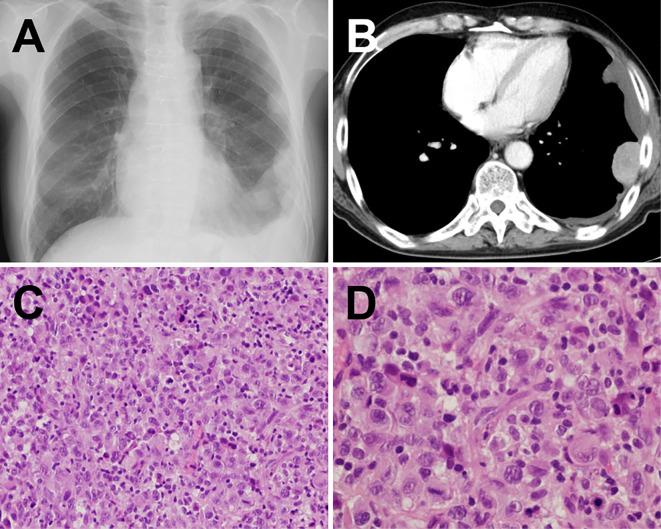

Primary pericardial malignant mesothelioma is a very rare clinical entity and its prognosis is very poor. We herein report a 67-year-old man who presented with pericardial mesothelioma that was diagnosed 21 months after the onset of cardiac tamponade as the initial manifestation. Despite undergoing pericardiocentesis and surgical pericardial fenestration at the onset of cardiac tamponade, we were unable to make a conclusive diagnosis of mesothelioma based on the cytological and histological findings. This unusual case had a relatively long progression-free period without treatment before the appearance of pleural tumors that showed the histological features of malignant sarcomatoid mesothelioma.

原发性心包恶性间皮瘤是一种非常罕见的临床病症,其预后非常差。我们在此报告一名67岁男性,他以心包间皮瘤就诊,在心脏压塞作为初始表现出现21个月后被诊断出来。尽管在心脏压塞发作时进行了心包穿刺术和外科心包开窗术,但根据细胞学和组织学检查结果,我们仍无法对间皮瘤做出明确诊断。这个不寻常的病例在出现具有恶性肉瘤样间皮瘤组织学特征的胸膜肿瘤之前,有一段相对较长的未经治疗的无进展期。